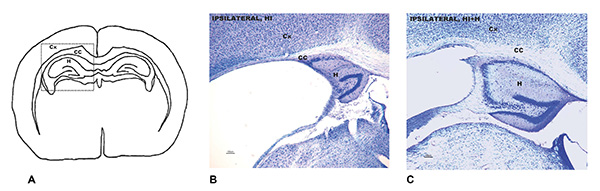

A: zona del cerebro afectada por la lesión cerebral por hipoxia e isquemia. B: Análisis neuropatológico que muestra el daño cerebral en ratones adultos que siendo bebés sufrieron la lesión y no recibieron estimulación sensorial. C: Análisis neuropatológica de la misma zona en los ratones adultos que sí la recibieron. (Foto: UAB)

Los resultados muestran que esta intervención ejerce una notable protección neurológica en ambos sexos a lo largo de la vida, pero es especialmente positiva en el sexo masculino, destacan las investigadoras. En este sexo, el análisis histopatológico mostró un daño cerebral un 50% menor que en los ratones no sometidos a la estimulación. En las hembras fue de un tercio. La protección neurológica en ambos sexos se correlacionó con mejoras en las capacidades funcionales, a nivel de reflejos, y permitió mejorar los resultados de memoria.

Por áreas cerebrales, la región involucrada en el control motor y el aprendizaje y la memoria -el caudado-putamen-, fue la que registró una mayor diferencia en machos, con un 80% menos de afectación. En hembras, la principal mejora fue la disminución, en un 66%, de la atrofia del cuerpo calloso, que permite a los dos hemisferios cerebrales trabajar de forma conjunta y complementaria.